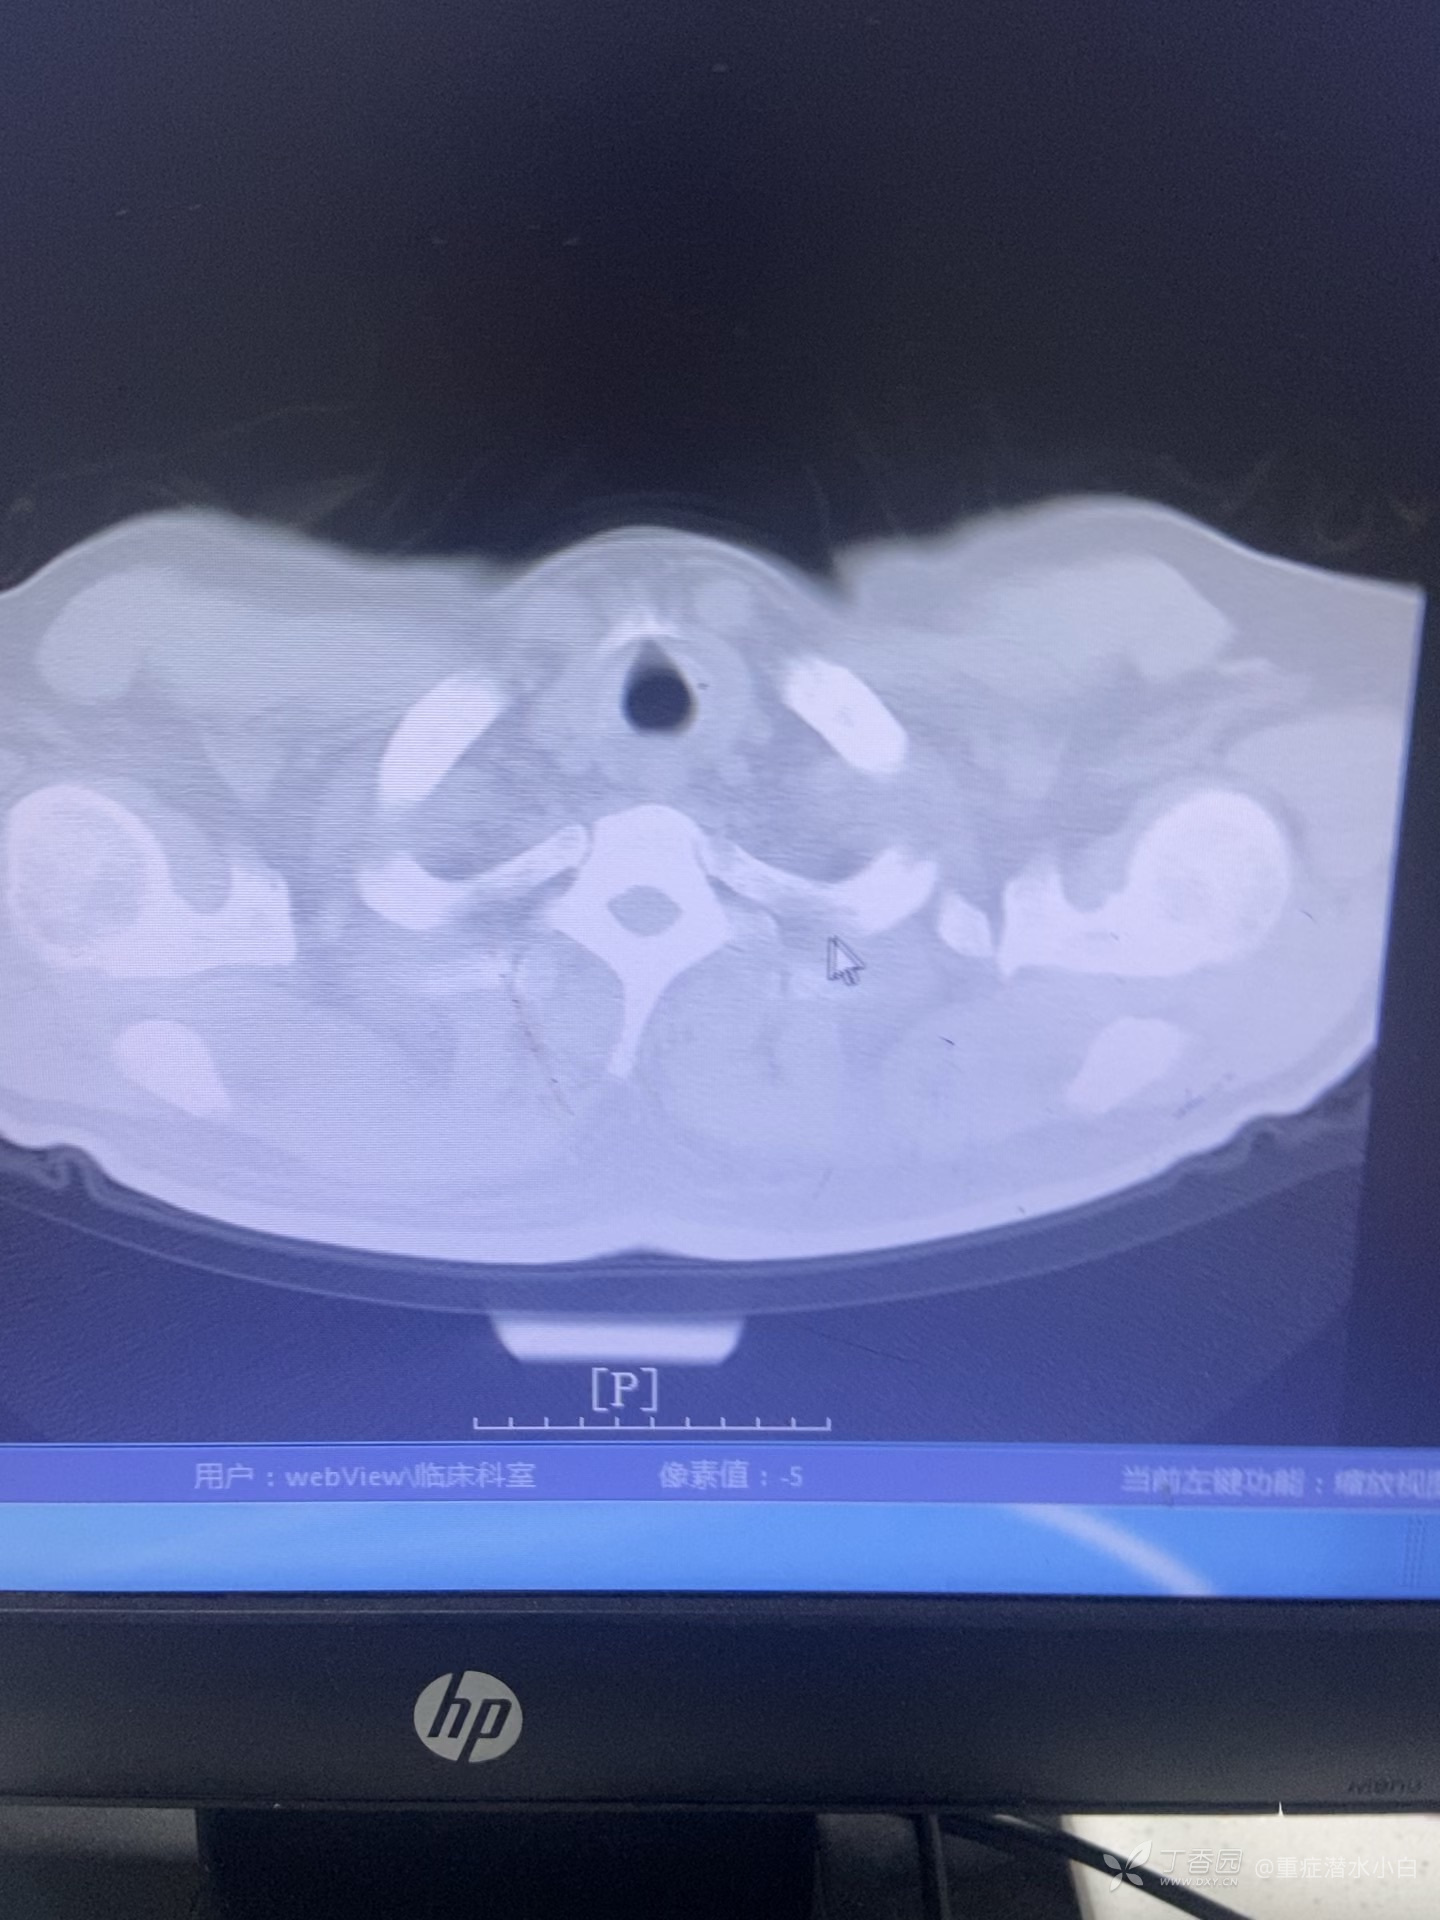

肺右叶奇叶形成

李梦杰huxi 达人已点赞分享一个头一次见到的CT影像:

肺奇叶,主要发生在肺部,奇叶为肺的解剖变异的一种少见类型,发生率约为 0.5%,为一侧肺尖部发生的额外肺叶,多见于右肺。奇叶系胚胎发育时期奇静脉异常移行,将右肺上叶于肺尖处分隔成为两个部分,并使局部的脏壁层胸膜随之陷入,上肺叶的内侧部分即为奇叶。 CT定位像上可见奇裂呈细的线条影,由右肺尖部向内、向下达肺门上方,终点呈一倒置的逗点状,此点状圆形阴影代表奇静脉断面的垂直投影,而在肺尖起点胸膜反折处,有时可见一小的三角形尖状突起。